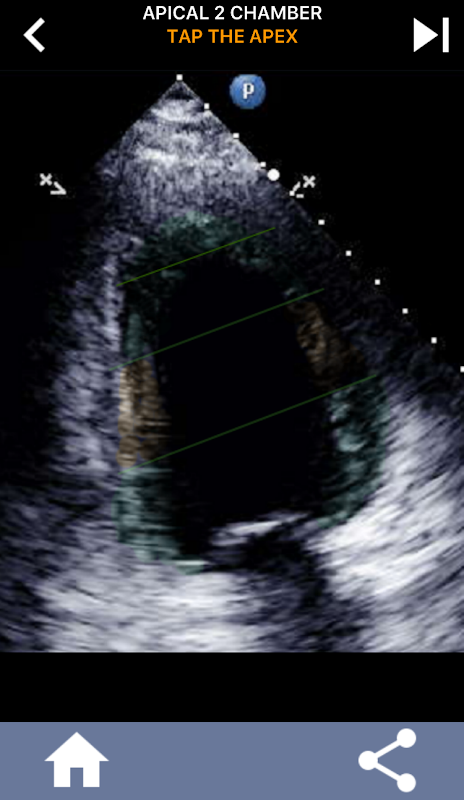

このアプリは、AHAセグメント心筋を示すすべてのエコービューが含まれており、正しいセグメントをタップするようにあなたをクイズします。私は個人的には、繰り返しのクイズはすぐに私が主題を学ぶ/暗記する必要があるときに私のために最も効果的であるとわかります。あなたがエコー/ TTEを勉強している超音波学生であるならば、私はこれがあなたの研究への素晴らしい補完物であると思います。